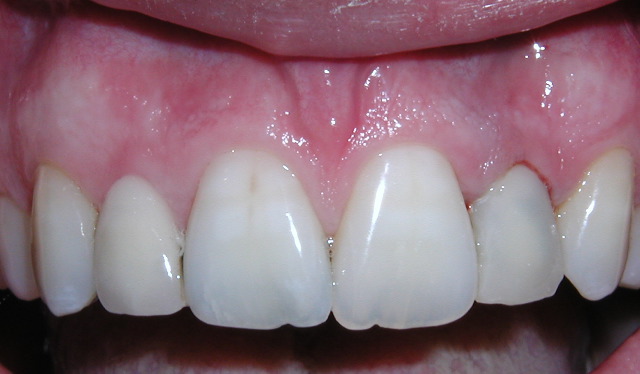

| Missing tooth | Implant placed |

| Temporary Crown | X-ray |

This procedure allows the placement of an implant with a temporary crown on the same day with no need for sutures. There is so little discomfort that most patients go back to work and use only mild "over the counte" type medications.